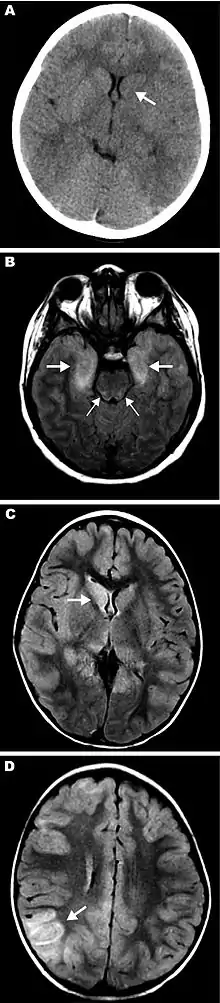

Eastern equine encephalitis (EEE), commonly called Triple E or sleeping sickness (not to be confused with African trypanosomiasis), is a disease caused by a zoonotic mosquito vectored Togavirus that is present in North, Central, and South America, and the Caribbean. EEE was first recognized in Massachusetts, United States, in 1831, when 75 horses died mysteriously of viral encephalitis. Epizootics in horses have continued to occur regularly in the United States. It can also be identified in donkeys and zebras. Due to the rarity of the disease, its occurrence can cause economic impact beyond the cost of horses and poultry.[1] EEE is found today in the eastern part of the United States and is often associated with coastal plains. It can most commonly be found in East Coast and Gulf Coast states.[2] In Florida, about one to two human cases are reported a year, although over 60 cases of equine encephalitis are reported. In years in which conditions are favorable for the disease, the number of equine cases is over 200.[3] Diagnosing equine encephalitis is challenging because many of the symptoms are shared with other illnesses and patients can be asymptomatic. Confirmations may require a sample of cerebral spinal fluid or brain tissue, although CT scans and MRI scans are used to detect encephalitis. This could be an indication that the need to test for EEE is necessary. If a biopsy of the cerebral spinal fluid is taken, it is sent to a specialized laboratory for testing.[4]

- Deresiewicz RL, Thaler SJ, Hsu L, Zamani AA (1997). "Clinical and neuroradiographic manifestations of eastern equine encephalitis". N. Engl. J. Med. 336 (26): 1867–74. doi:10.1056/NEJM199706263362604. PMID 9197215.